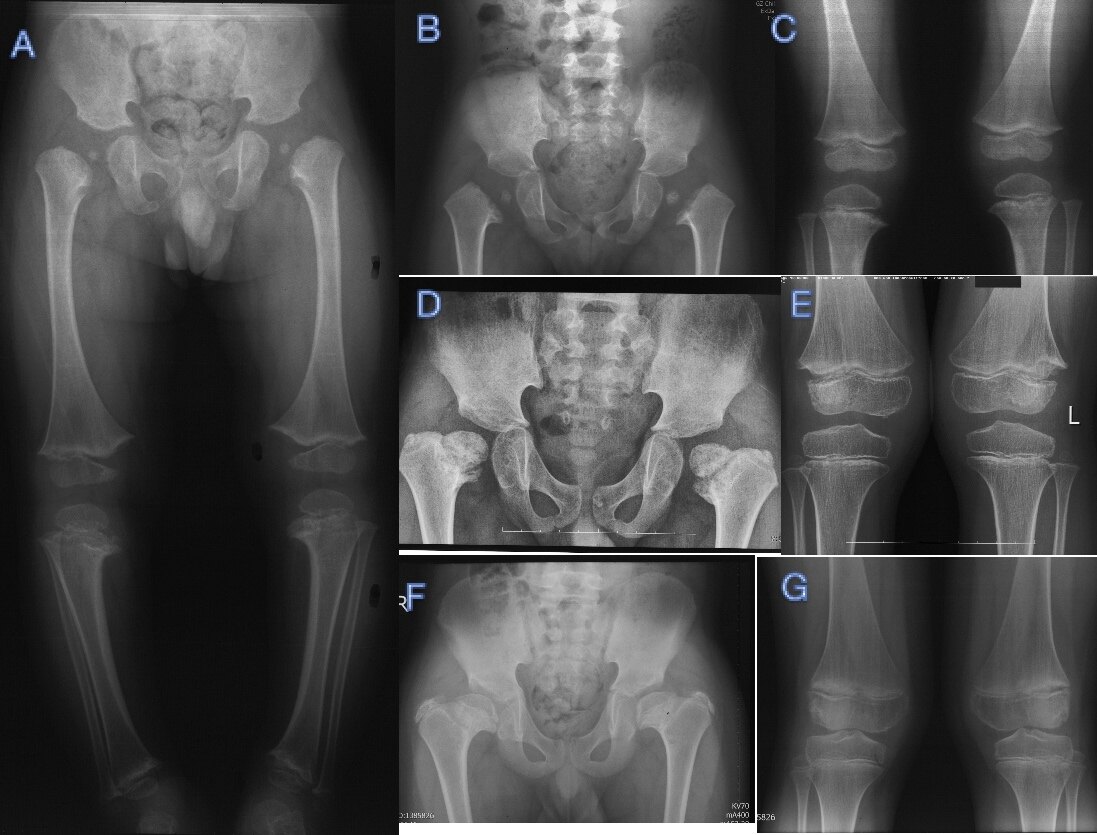

一例基因检测证实为 COL10A1 突变的 MCDS 患者 X 线表现,其膝内翻经过支具治疗,干 骺端异常改善,但髋内翻进展:A 初诊时 2 岁;BC3 岁;DE6 岁;FG11 岁。

干骺端软骨发育不良,Schmid型(MCDS )是最常见的、最轻型的 MCD 类型,与最严重的 Jansen 型同为常染色体显性(AD)遗传。MCDS 以轻度身材矮小(短肢型)、膝内翻(O 型腿)、髋内翻为主的骨科表现,常在开始走路时(1-2 岁)因 O 型腿和(或)摇摆步态就诊。随着年龄增大,O 型腿有自行或非手术治疗改善可能,但髋内翻常需截骨手术治疗。上肢长骨干骺端可出现下肢同样改变,但常无需特别处理,脊柱改变少见,偶见扁平椎和终板不平整。

骨科以治疗髋内翻和膝内翻为主,当出现摇摆步态(鸭步)、疼痛、髋内翻进行性加重时常需手术治疗,支具、牵引、物理治疗等保守治疗多无效;髋内翻多采用股骨近端外翻截骨手术治疗,有多种术式,其目的都在于改善力线,恢复髋外展肌力臂,刺激股骨头和颈骨缺损愈合;MCDS 膝内翻有一定自愈能力,支具可用于轻症患者治疗,生长期儿童严重的膝内翻畸形可通过骨骺阻滞术治疗。严重髋内翻多伴随着代偿性膝外翻,处理髋内翻时要同时处理膝外翻为宜。